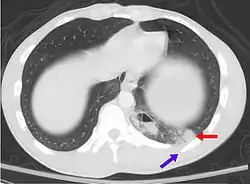

- Pulmonary contusion